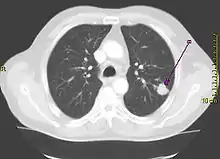

يعدّ التدخين هو السبب الأول لحالات سرطان الرئة حيث يشكل حوالي 85% كسبب رئيسي للإصابة بذلك السرطان وفقط حوالي 10-15٪ من حالات السرطان تحدث عند الأشخاص الذين لم يدخنوا أبدًا.[9][10][11][12] غالبًا ما تنتج هذه الحالات عن مجموعة من العوامل الوراثية مثل التعرض لغاز الرادون، أو الأسبستوس، أو التدخين غير المباشر، أو أشكال أخرى من تلوث الهواء. يمكن رؤية سرطان الرئة على الصور الشعاعية للصدر والتصوير المقطعي المحوسب (CT). يتم تأكيد التشخيص عن طريق الخزعة.[13]

- مسح مقطعي (الأشعة المقطعية)[48]